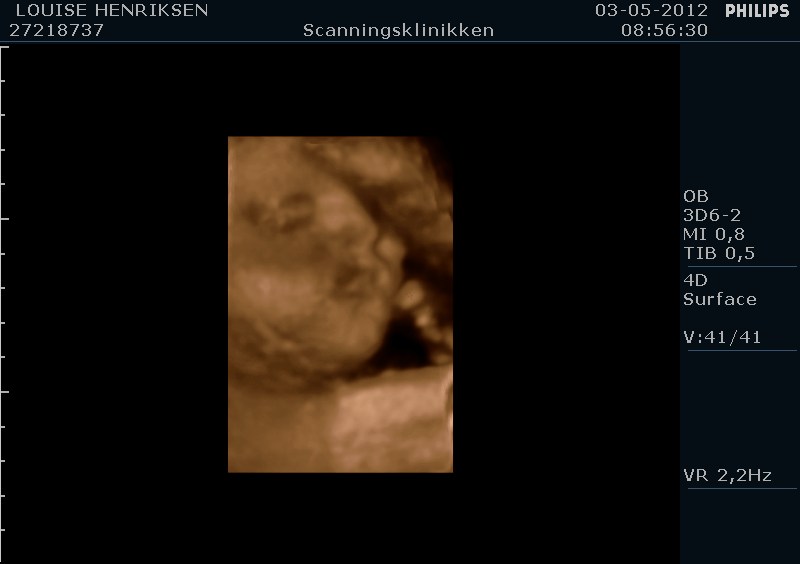

I dag skulle manden overraskes med en 4 d scanning.... og hans far var også med det var også en overraskelse, samt den lille prins....han fik bind for øjene og vi kørte mod scanning klinikken.... vi fik nogle gode sekvenser af bettemanden.. men han fylder en del derinde nu, så billederne blev ikke voldsomt gode.. men nogle fik vi dag...jeg skulle i morgen være 32 fulde uger.. mne scanningen i dag vidste34+4 dage yiarks.... jeg skal til at være færdig med den bachelor..... han vejede efter målene 1871 gram.....

så han var en fin basse...

Sikke nogle fine billeder